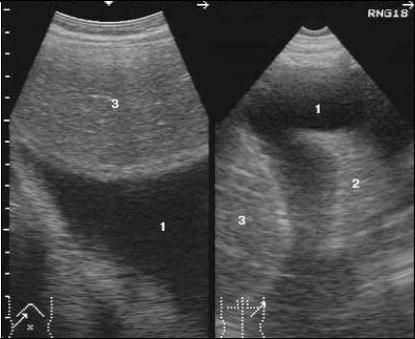

Наиболее частым показанием для ультразвукового исследования грудной полости является определение наличия жидкости в плевральной полости (рис. 1).

Рис. 1. Сонограммы грудной стенки доступом из подреберья (а) и через межреберный промежуток (б).

1 – жидкость в плевральной полости;

2– поджатое легкое;

3- печень